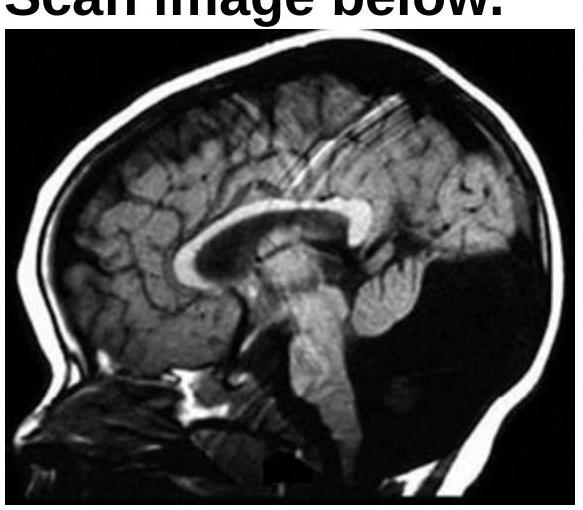

Identify the diagnosis using the MRI provided.

Explanation: ***Chiari type 1 malformation*** - The sagittal MRI image clearly shows the **cerebellar tonsils prolapsing below the foramen magnum** into the cervical spinal canal, which is the hallmark of a Chiari type 1 malformation. - This condition can lead to symptoms like headaches, neck pain, and neurological deficits due to compression of the brainstem and spinal cord. *Dandy-Walker malformation* - This malformation involves the **agenesis or hypoplasia of the cerebellar vermis** and persistent cystic dilation of the fourth ventricle, creating a large posterior fossa cyst. - The image does not show an enlarged posterior fossa with a cystic fourth ventricle or a severely hypoplastic vermis. *Vein of Galen malformation* - This is a **rare congenital vascular malformation** involving a direct arteriovenous shunt without an intervening capillary bed, typically presenting as an enlarged vein of Galen. - The provided image is a sagittal view demonstrating cerebellar tonsillar herniation, not a prominent or malformed vein of Galen. *Agenesis of the corpus callosum* - This condition is characterized by the **partial or complete absence of the corpus callosum**, the band of white matter connecting the two cerebral hemispheres. - On sagittal MRI, this would show absence of the corpus callosum and typically radial gyral patterns, which are not seen in this image.